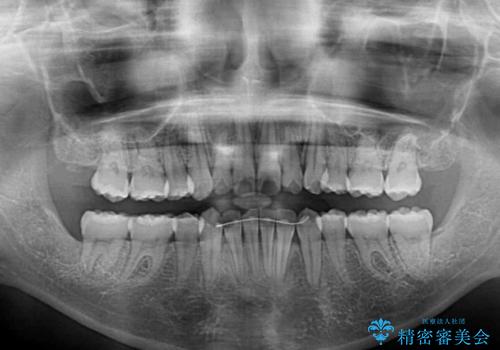

- 以前の矯正治療の後戻りにより、上下の前歯がでこぼこになってしまったことを気にして来院された患者様です。

口元がこれ以上突出することなく前歯の叢生が改善できるよう、歯と歯の間を削ってスペースを獲得し、インビザラインを用いて整えていくこととしました。

目安の装着時間である1日22時間をしっかりと実践してくださり、半年強という短期間で治療を終えることができました。